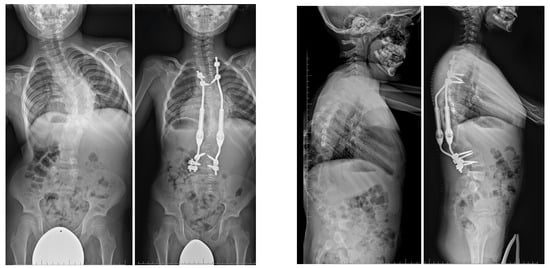

7.3.4. Growing Rod Systems

7.3.5. Impact on Pulmonary Development and Vertical Expandable Prosthetic Titanium Rib (VEPTR)